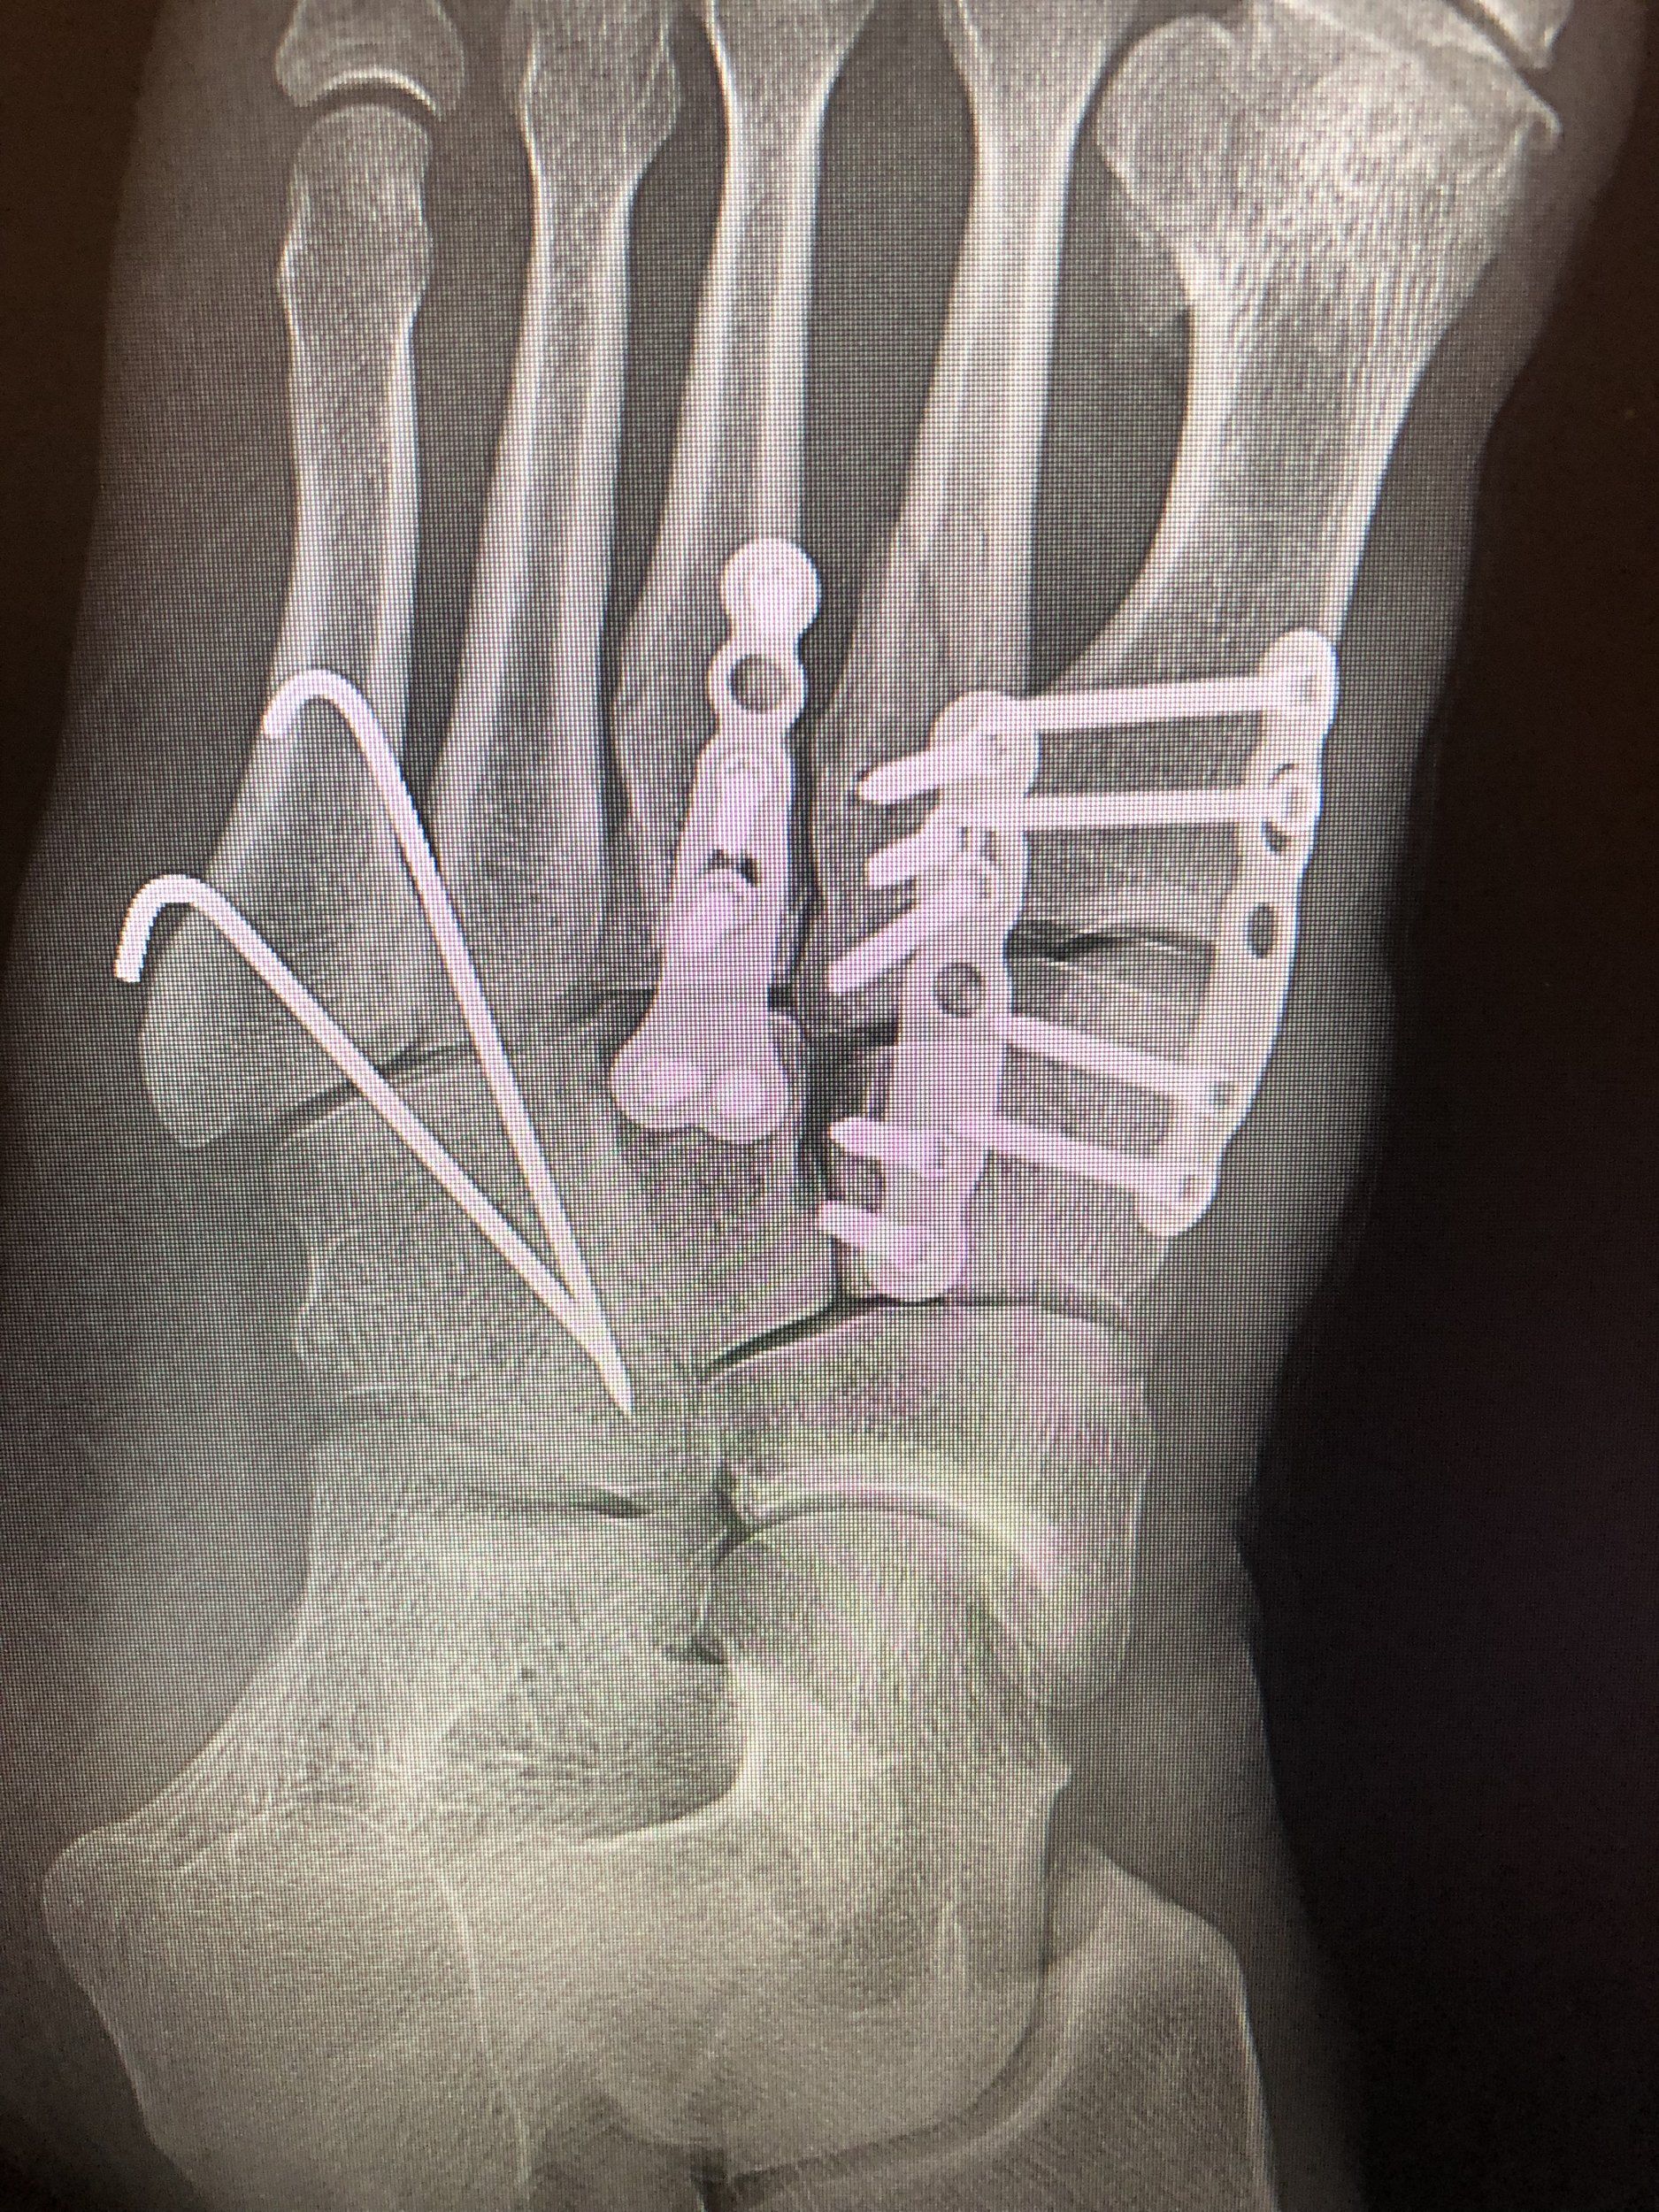

Fick 7 skruvar och en fin titanplatta i min klöv. Nu ett drygt år senare ska jag testa att knö ner den i en slalompjäxa. Det blir spännande.

plattorna tar en viss plats...

plattorna tar en viss plats...

åter till svedala efter milslånga promenader fyra dagar i london. min lisfranc-skadade fot avbildad ovan stod emot utan minsta protest, så här snart tre år senare.

i mitt fall har efter fem år åtminstone två av tre plattor gått av, liksom ett antal skruvar. ändå ingen längtan att ta bort dem. trots att man lär få belasta fullt efter ett sådant ingrepp.

en olägenhet är att det blir viss trängsel i slalompjäxor, men ändå mycket nöjd totalt sett.

en olägenhet är att det blir viss trängsel i slalompjäxor, men ändå mycket nöjd totalt sett.